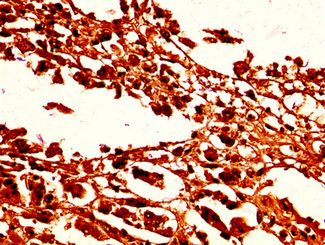

IHC image of CSB-PA010378OA96nforHU diluted at 1:50 and staining in paraffin-embedded human melanoma performed on a Leica BondTM system. After dewaxing and hydration, antigen retrieval was mediated by high pressure in a citrate buffer (pH 6.0). Section was blocked with 10% normal goat serum 30min at RT. Then primary antibody (1% BSA) was incubated at 4°C overnight. The primary is detected by a biotinylated secondary antibody and visualized using an HRP conjugated SP system.